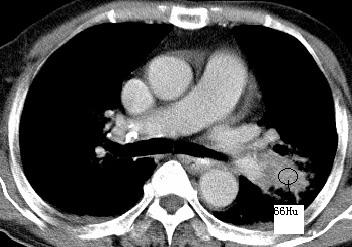

以下是引用xianxianzhongyi在2008-4-20 14:44:00的发言:[br]本人愚见:次病例短短两月的时间,呈现如此大面积实变,病变增长过于迅速,此其一。其二,病变在动脉早期既有明显强化。其三,左上叶后段及下叶背段多叶受累。其四,肺门及纵隔内未见明显肿大的淋巴结。估计层面较厚段支气管显示不清。 诊断:炎性实变可能性大。

以下是引用光影相伴在2008-4-20 14:39:00的发言:[br]支持:1)左侧中央型肺癌伴左肺上叶阻塞性肺炎。、[br] 2)双侧少量胸腔积液。